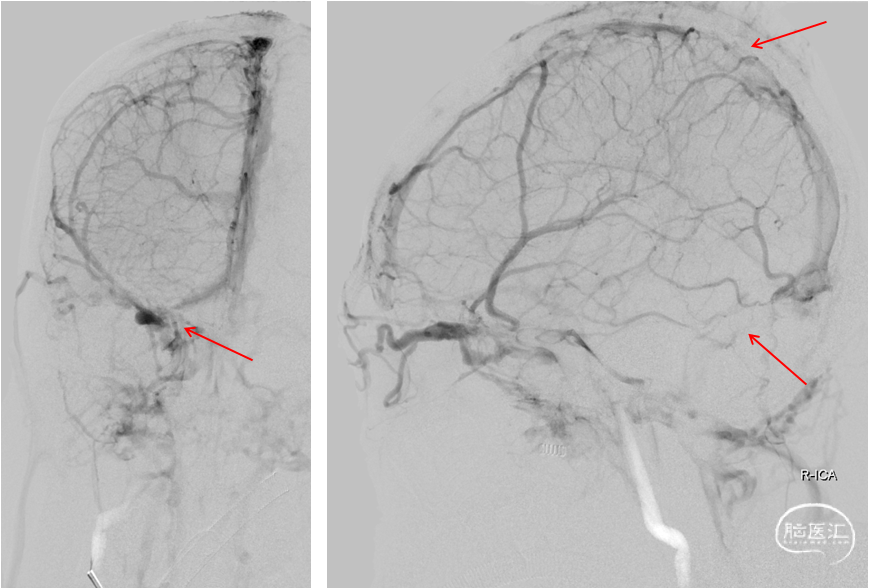

复查造影:上矢状窦显影明显改善,右侧横窦及乙状窦显影良好,静脉回流良好

颅内正侧位造影:上矢状窦显影明显改善,右侧横窦及乙状窦显影良好,静脉回流良好

复查造影:上矢状窦显影明显改善,右侧横窦及乙状窦显影良好,静脉回流良好。行平板CT颅内未见出血。